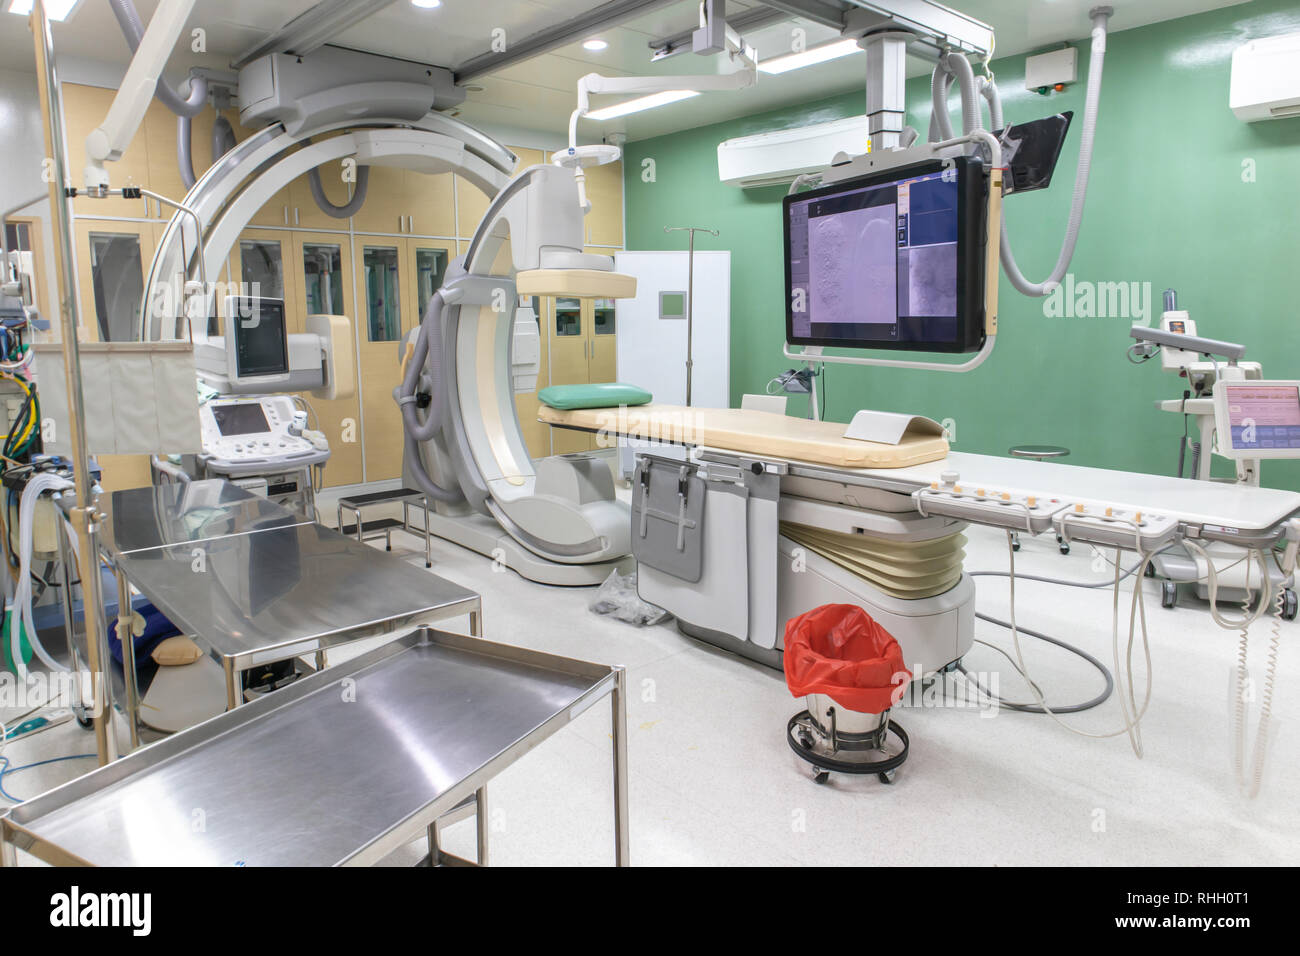

Digital Subtraction Angiography Room, DSA lab, operating room with X-ray medical scan in hospital. Stock Photohttps://www.alamy.com/image-license-details/?v=1https://www.alamy.com/digital-subtraction-angiography-room-dsa-lab-operating-room-with-x-ray-medical-scan-in-hospital-image234557835.html

Digital Subtraction Angiography Room, DSA lab, operating room with X-ray medical scan in hospital. Stock Photohttps://www.alamy.com/image-license-details/?v=1https://www.alamy.com/digital-subtraction-angiography-room-dsa-lab-operating-room-with-x-ray-medical-scan-in-hospital-image234557835.htmlRFRHH0WF–Digital Subtraction Angiography Room, DSA lab, operating room with X-ray medical scan in hospital.

Digital Subtraction Angiography Room, DSA lab, operating room with X-ray medical scan in hospital. Stock Photohttps://www.alamy.com/image-license-details/?v=1https://www.alamy.com/digital-subtraction-angiography-room-dsa-lab-operating-room-with-x-ray-medical-scan-in-hospital-image234557793.html

Digital Subtraction Angiography Room, DSA lab, operating room with X-ray medical scan in hospital. Stock Photohttps://www.alamy.com/image-license-details/?v=1https://www.alamy.com/digital-subtraction-angiography-room-dsa-lab-operating-room-with-x-ray-medical-scan-in-hospital-image234557793.htmlRFRHH0T1–Digital Subtraction Angiography Room, DSA lab, operating room with X-ray medical scan in hospital.

Digital Subtraction Angiography Room, DSA lab, operating room with X-ray medical scan in hospital. Stock Photohttps://www.alamy.com/image-license-details/?v=1https://www.alamy.com/digital-subtraction-angiography-room-dsa-lab-operating-room-with-x-ray-medical-scan-in-hospital-image234557799.html

Digital Subtraction Angiography Room, DSA lab, operating room with X-ray medical scan in hospital. Stock Photohttps://www.alamy.com/image-license-details/?v=1https://www.alamy.com/digital-subtraction-angiography-room-dsa-lab-operating-room-with-x-ray-medical-scan-in-hospital-image234557799.htmlRFRHH0T7–Digital Subtraction Angiography Room, DSA lab, operating room with X-ray medical scan in hospital.

Digital Subtraction Angiography Room, DSA lab, operating room with X-ray medical scan in hospital. Stock Photohttps://www.alamy.com/image-license-details/?v=1https://www.alamy.com/digital-subtraction-angiography-room-dsa-lab-operating-room-with-x-ray-medical-scan-in-hospital-image234557821.html

Digital Subtraction Angiography Room, DSA lab, operating room with X-ray medical scan in hospital. Stock Photohttps://www.alamy.com/image-license-details/?v=1https://www.alamy.com/digital-subtraction-angiography-room-dsa-lab-operating-room-with-x-ray-medical-scan-in-hospital-image234557821.htmlRFRHH0W1–Digital Subtraction Angiography Room, DSA lab, operating room with X-ray medical scan in hospital.

Digital Subtraction Angiography Room, DSA lab, operating room with X-ray medical scan in hospital. Stock Photohttps://www.alamy.com/image-license-details/?v=1https://www.alamy.com/digital-subtraction-angiography-room-dsa-lab-operating-room-with-x-ray-medical-scan-in-hospital-image234557830.html

Digital Subtraction Angiography Room, DSA lab, operating room with X-ray medical scan in hospital. Stock Photohttps://www.alamy.com/image-license-details/?v=1https://www.alamy.com/digital-subtraction-angiography-room-dsa-lab-operating-room-with-x-ray-medical-scan-in-hospital-image234557830.htmlRFRHH0WA–Digital Subtraction Angiography Room, DSA lab, operating room with X-ray medical scan in hospital.